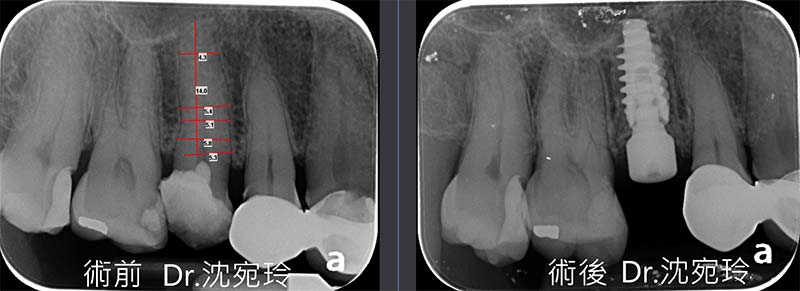

此次的案例為即拔即種,除了拔牙前X光片的審慎評估,還有拔牙時使用特殊器械,致力於保存頰側骨板和拔牙窩的完整度!!讓勝算多一籌!!

牙齒在拔牙的當下,身體就開始展開強烈的癒合機制,自發性長骨頭、自發性長牙肉,我們利用這強烈癒合的機制,巧妙性的除了保存現有頰側骨板的完整性,另外還特地選用瑞典諾堡科植體Nobel active,具有自攻的螺紋特性,在植入植體時得到35N/cm扭力的植體初始穩定度。